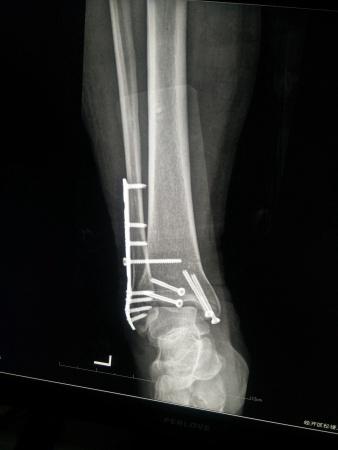

左三踝骨折手术治疗

患者女,外伤后左踝关节活动受限1小时入院,

入院后查体:左踝关节肿胀,活动受限,行DR及左踝关节CT检查,如下图,手术待肿胀消退后行手术治疗,目前愈合良好,请问问各位老师,好久可以下地呀, 下胫腓联合镙钉3个月取呀,

这个下胫腓螺钉真的没有必要打,另外后踝的两枚螺钉怪怪的,从后往前打的,看着钉子帽偏内侧,这个应该在外侧才对,

下胫腓联合单钉固定小心断钉